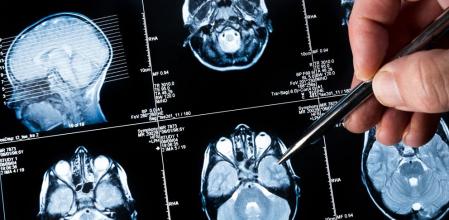

Administrar la inmunoterapia antes de la cirugía para extirpar el tumor ha mejorado las tasas de supervivencia; el resultado debe confirmarse en estudios más amplios

Los fármacos ayudan a los linfocitos del sistema inmunitario a entrar en el tumor para destruir las células cancerosas